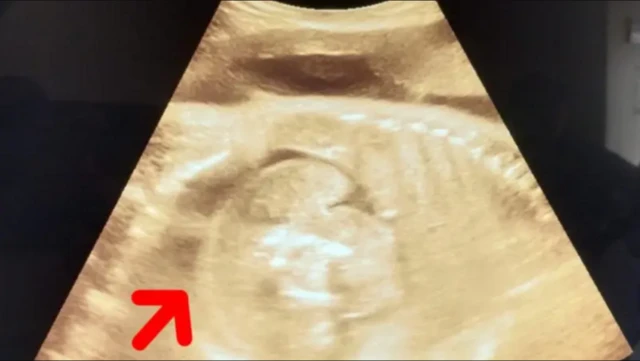

ਤਸਵੀਰ ਸਰੋਤ, quasim sheikh

ਬੁਲਢਾਣਾ ਦੀ 32 ਸਾਲਾ ਔਰਤ ਜੋ 8 ਮਹੀਨਿਆਂ ਦੀ ਗਰਭਵਤੀ ਹੈ, ਉਹ ਸਰਕਾਰੀ ਹਸਪਤਾਲ ਸੋਨੋਗ੍ਰਾਫੀ ਕਰਵਾਉਣ ਪਹੁੰਚੀ ਸੀ।

ਜਾਂਚ ਤੋਂ ਪਤਾ ਲੱਗਿਆ ਕਿ ਗਰਭ ਵਿਚਲੇ ਭਰੂਣ ਦੇ ਅੰਦਰ ਵੀ ਇੱਕ ਭਰੂਣ ਹੈ।

ਜਦੋਂ ਡਾਕਟਰਾਂ ਅਤੇ ਮਾਹਰਾਂ ਦੀ ਟੀਮ ਨੇ ਇੱਕ ਵਾਰ ਮੁੜ ਤੋਂ ਸੋਨੋਗ੍ਰਾਫੀ ਕੀਤੀ ਤਾਂ ਫਿਰ ਦੁਬਾਰਾ ਗਰਭ ਵਿਚਲੇ ਬੱਚੇ ਦੇ ਪੇਟ ਵਿੱਚ ਭਰੂਣ ਸਾਫ ਨਜ਼ਰ ਆਇਆ।

ਬੁਲਢਾਣਾ ਜ਼ਿਲ੍ਹੇ ਦੇ ਸਿਵਲ ਸਰਜਨ ਡਾਕਟਰ ਭਗਵਤ ਭਾਸੁਰੀ ਨੇ ਬੀਬੀਸੀ ਮਰਾਠੀ ਨੂੰ ਇਸ ਘਟਨਾ ਬਾਰੇ ਦੱਸਿਆ ਹੈ।

ਡਾ. ਭਾਸੁਰੀ ਨੇ ਕਿਹਾ, "ਸੋਨੋਗ੍ਰਾਫੀ ਟੈਸਟ ਬਾਅਦ ਇਹ ਦੇਖਿਆ ਗਿਆ ਕਿ ਔਰਤ ਦੇ ਪੇਟ ਵਿੱਚ ਬੱਚਾ ਹੈ ਅਤੇ ਉਸ ਬੱਚੇ ਦੇ ਪੇਟ ਵਿੱਚ ਇੱਕ ਬੱਚਾ ਹੈ। ਵੈਸੇ ਤੁਸੀਂ ਇਸ ਨੂੰ ਬੱਚਾ ਤਾਂ ਨਹੀਂ ਕਹਿ ਸਕਦੇ ਕਿਉਂਕਿ ਇਹ ਭਰੂਣ ਦਾ ਮਾਸ ਹੈ। ਇਹ ਇੱਕ ਤਰ੍ਹਾਂ ਨਾਲ, ਮਾਸ ਦਾ ਟੁੱਕੜਾ ਹੈ।

ਇਹ ਜਿਉਂਦਾ ਬੱਚਾ ਨਹੀਂ ਹੈ। ਇਸ ਦਾ ਦਿਲ ਨਹੀਂ ਧੜਕ ਰਿਹਾ। ਇਸ ਨੂੰ ਬੱਚਾ ਇਸ ਲਈ ਕਿਹਾ ਗਿਆ ਕਿਉਂਕਿ ਇਹ ਬੱਚੇ ਵਰਗਾ ਦਿਸਦਾ ਹੈ।

"ਇਹ ਗੇਂਦਨੁਮਾ ਚੀਜ਼ ਵੱਧ ਫੁੱਲ ਰਹੀ ਹੈ ਕਿਉਂਕਿ ਇਸ ਤੱਕ ਖੂਨ ਦੀ ਸਪਲਾਈ ਹੋ ਰਹੀ ਹੈ, ਇਸ ਨੂੰ ਫੀਟਸ ਇਨ ਫੀਟੂ ਕਹਿੰਦੇ ਹਨ।"